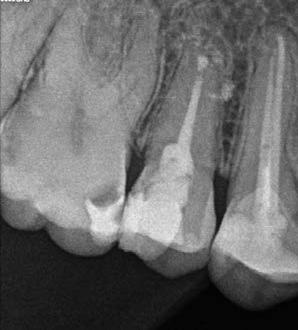

1. a-n. ábrák: Preoperatív CBCT-felvétel a bal alsó 6-os (3.6) fogról. Az axialis (a), coronalis (b) és sagittalis (c) nézeteken a mezialis és distalis gyökerek apicalis harmada körül sugáráteresztő zóna és ép buccalis corticalis csont látható. Egy olyan sablont terveztünk, amely jelezte a csontablak határait az apicalis terület pontos elérése érdekében (d). A mikrosebészeti bevatkozás során a sablont a helyére illesztettük (e), a csontablak határait megjelöltük (f) egy Piezotome CUBE LED kézi-darabba fogott fűrésszel, majd kivágtuk és eltávolítottuk (g és h) az apicalis területhez történő hozzáférés, illetve a mezialis és distalis gyökerek rezekciójának, retrográd preparációjának és retrográd gyökértömésének elvégzése érdekében (i). Végezetül a csontablakot visszaillesztettük és kollagén szivaccsal stabilizáltuk (j). A műtét után közvetlenül készített röntgenfelvétel a 3.6-os fogról (k). A kétéves kontroll során készített CBCT-felvétel: axialis (l), coronalis (m) és sagittalis (n) nézetek.

Egy 63 éves páciens korábban már kezelt bal alsó első nagyőrlőfogából (3.6) eredő mérsékelt fájdalom miatt kereste fel rendelőnket. A kórtörténetében panasza szempontjából releváns információ nem szerepelt. Az elkészült CBCT-felvételen a korábbi kezelések során észre nem vett, jelenleg feltáratlan meziobuccalis csatornát, valamint a mezialis és distalis gyökerek körül kialakult periapicalis elváltozást, és ezt a léziót borító intakt buccalis corticalis csontlemezt láttunk.

Klinikai vizsgálat során vertikális kopogtatási érzékenységet jelzett. A fog körül mérhető szondázási mélység és a fogmobilitás fiziológiás volt. A CBCT-felvételen nem észleltünk a csontos regeneráció megindulására utaló jeleket (1. a–c. ábrák). A korábban gyökérkezelt, gyökértömött és revideált 3.6-os fog esetében az alábbi diagnózis került felállításra: periodontitis periapicalis symptomatica. A panaszokat okozó fog további ellátása során navigált endodonciai mikrosebészetet kívántunk alkalmazni. Az alsó állcsontról intraorális szkent (TRIOS, 3Shape) készítettünk, és a felszíni topográfiát tartalmazó STL fájlt, valamint a CBCT-felvétel készítése során nyert DICOM fájlokat a Blue Sky Bio szoftver segítségével egyesítettük. A sebészi sablon megtervezésére az így kapott háromdimenziós képet használtuk. A sablon kialakítása során arra törekedtünk, hogy a sablon egyértelműen meghatározza a gyökércsúcsi terület eléréséhez szükséges csontablak határait (1. d. ábra)